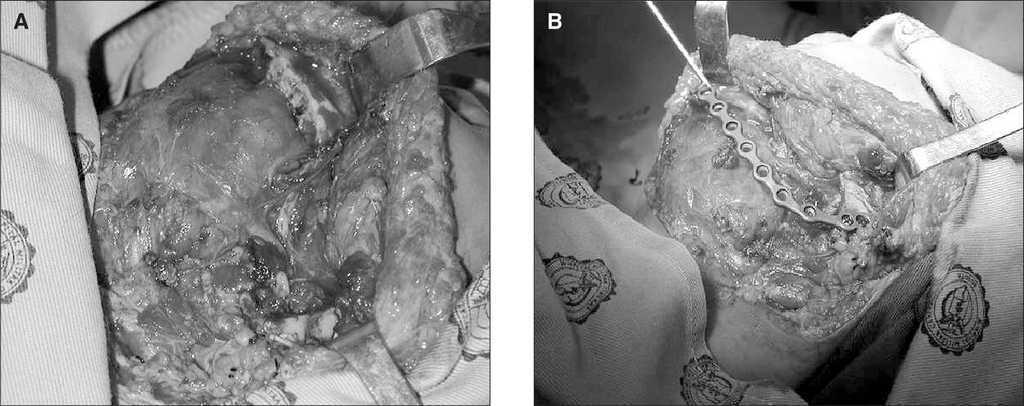

La tomografía computarizada (TC) realizada mostró una lesión de tejidos blandos que comprometía la hemimandíbula izquierda (fig. 2A y B). La biopsia de la lesión confirmó el diagnóstico de fibromixoma de origen odontogénico. Con este diagnóstico, se practicó resección completa macroscópica del tumor con reconstrucción con placa de mandíbula, por el servicio de cirugía plástica (fig. 3A y B).

Figura 3A y B. Procedimiento quirúrgico.